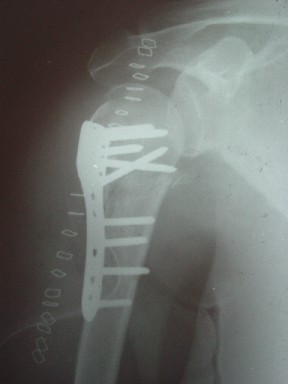

Клинические снимки - 3 недели после операции

с уважением М. Беренштейн

можно попытаться провести повторную закр. репозицию под ЭОПом с остеосинтезом LPHP , при невозможности закр. репозиции откр. репозиция и остеосинтез LPHP, Т-LCP, LCP-лист клевера